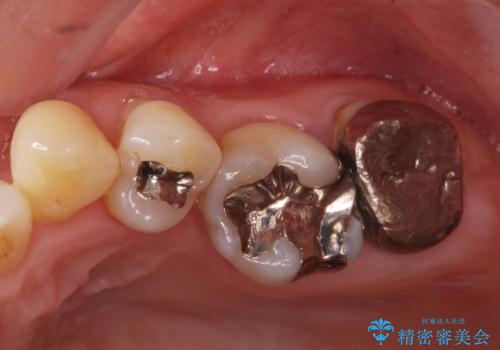

- 前歯(右上2)が黄色いとのことで来院。

レントゲンを撮ったところ前歯の被せ物が不適でした。

根管治療はご希望されなかったので(症状はなし)被せ物のやりかえ、右上2は被せ物の治療を行いました。